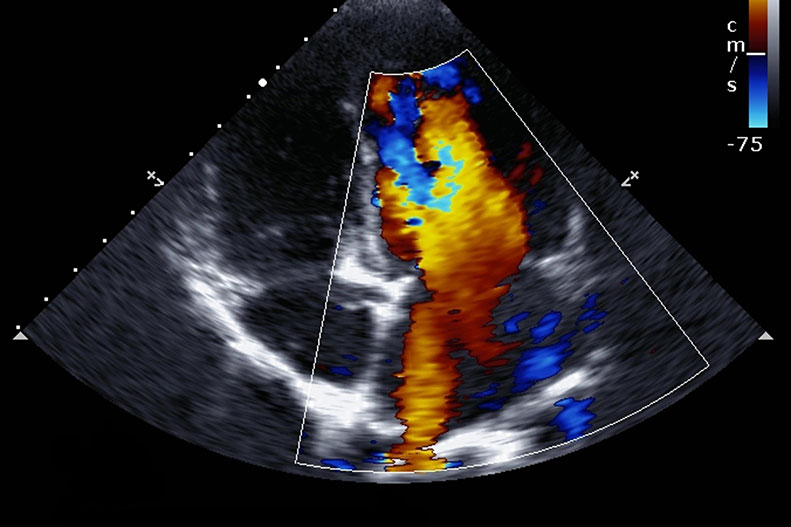

Echocardiography

Echocardiography stays the overwhelming imaging methodology for the opportune and costeffective assessment of heart structure and work. Regardless of the expanding accessibility of echocardiography for indicative and place of-care applications, there is impressive fluctuation in the availability, quality, what’s more, analytic utility of this test. The obtaining and translation of echocardiograms remains exceptionally subject to administrator experience, consequently making it a methodology overflowing with openings for expansion and normalization through AI. Given the total volume of clinical echocardiography information, there is abundant freedom for research furthermore, improvement of echocardiography AI stages. Advancements in such manner may further develop translation, normalization, what’s more, work process through computerized evaluation, recognizable proof of pathologic components (valve sickness, provincial divider movement irregularities, cardiomyopathies), and quick utilization of result information at the place of care.

The strength and prospect of echocardiography AI research is in the distinguishing proof of inconspicuous or unnoticed imaging highlights that might address subclinical sickness or show patient anticipation. Albeit the exhibition of AI models keeps on improving, recognize that AI should conquer a few significant difficulties before it very well may be applied securely in clinical practice. Likewise with any model, the quality and clinical attributes of the advancement information are essential contemplations.

Given the huge sum and intricacy of information related with an echocardiogram, a hearty echocardiography AI stage will require preparing and approval on countless concentrates on that envelop a wide scope of clinical attributes, pathologic provisions, ultrasound machine sellers, and picture quality.

Current investigations of echocardiography AI for the most part include generally little example measures that are restricted by institutional or geographic limits or even by brands of echocardiography machines, which hazards overfitting and restricting the generalizability of the subsequent stages. Moreover, echocardiography Artificial intelligence research has generally depended on human translation as the ground truth in spite of the inborn human changeability in translation also, estimation.

Artificial insight addresses an energizing freedom that is ready to upset the clinical act of echocardiography. Demonstrated echocardiography AI models will have the ability to work on quality, empower place of-care dynamic, and work with value in admittance to analytic devices. We expect that echocardiography AI will affect patient consideration, and we energetically anticipate clinical investigations that report worked on clinical results and cost-viability.